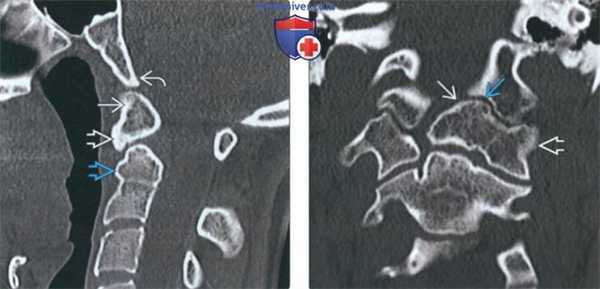

(Справа) Аксиальный КТ-срез подтверждает наличие прочного врожденного сращения ортотопичной зубовидной кости с передней дугой С1. Задняя дуга С1 сформирована полностью (здесь не видно). (Слева) КТ, сагиттальный-срез: сращение крупной дистопичной зубовидной кости с передней дугой С1. Вершина ската с признаками минимального ремоделирования (уплощена). Укороченный и закругленный зубовидный отросток диспластичен.

(Справа) На фронтальном КТ-срезе представлен случай эксцентричного сращения дистопичной зубовидной кости с левой половиной передней дуги С1 и его боковой массой. Обратите также внимание на наличие аномального неоартроза между зубовидной костью и левым мыщелком затылочной кости.в) Дифференциальная диагностика:

(Слева) На сагиттальной КТ в костном окне определяется слияние дистопической зубовидной кости с передней дугой С1. Вершина ската минимально ремоделирована (уплощена). Определяется дисплазия короткого и округлого зубовидного отростка.

(Справа) На корональной КТ в костном окне определяется эксцентрическое слияние дистопической зубовидной кости с передней дугой и боковой массой С1 слева. Обратите также внимание на патологический псевдосустав между зубовидной костью и левым затылочным мыщелком.1. Проявления: